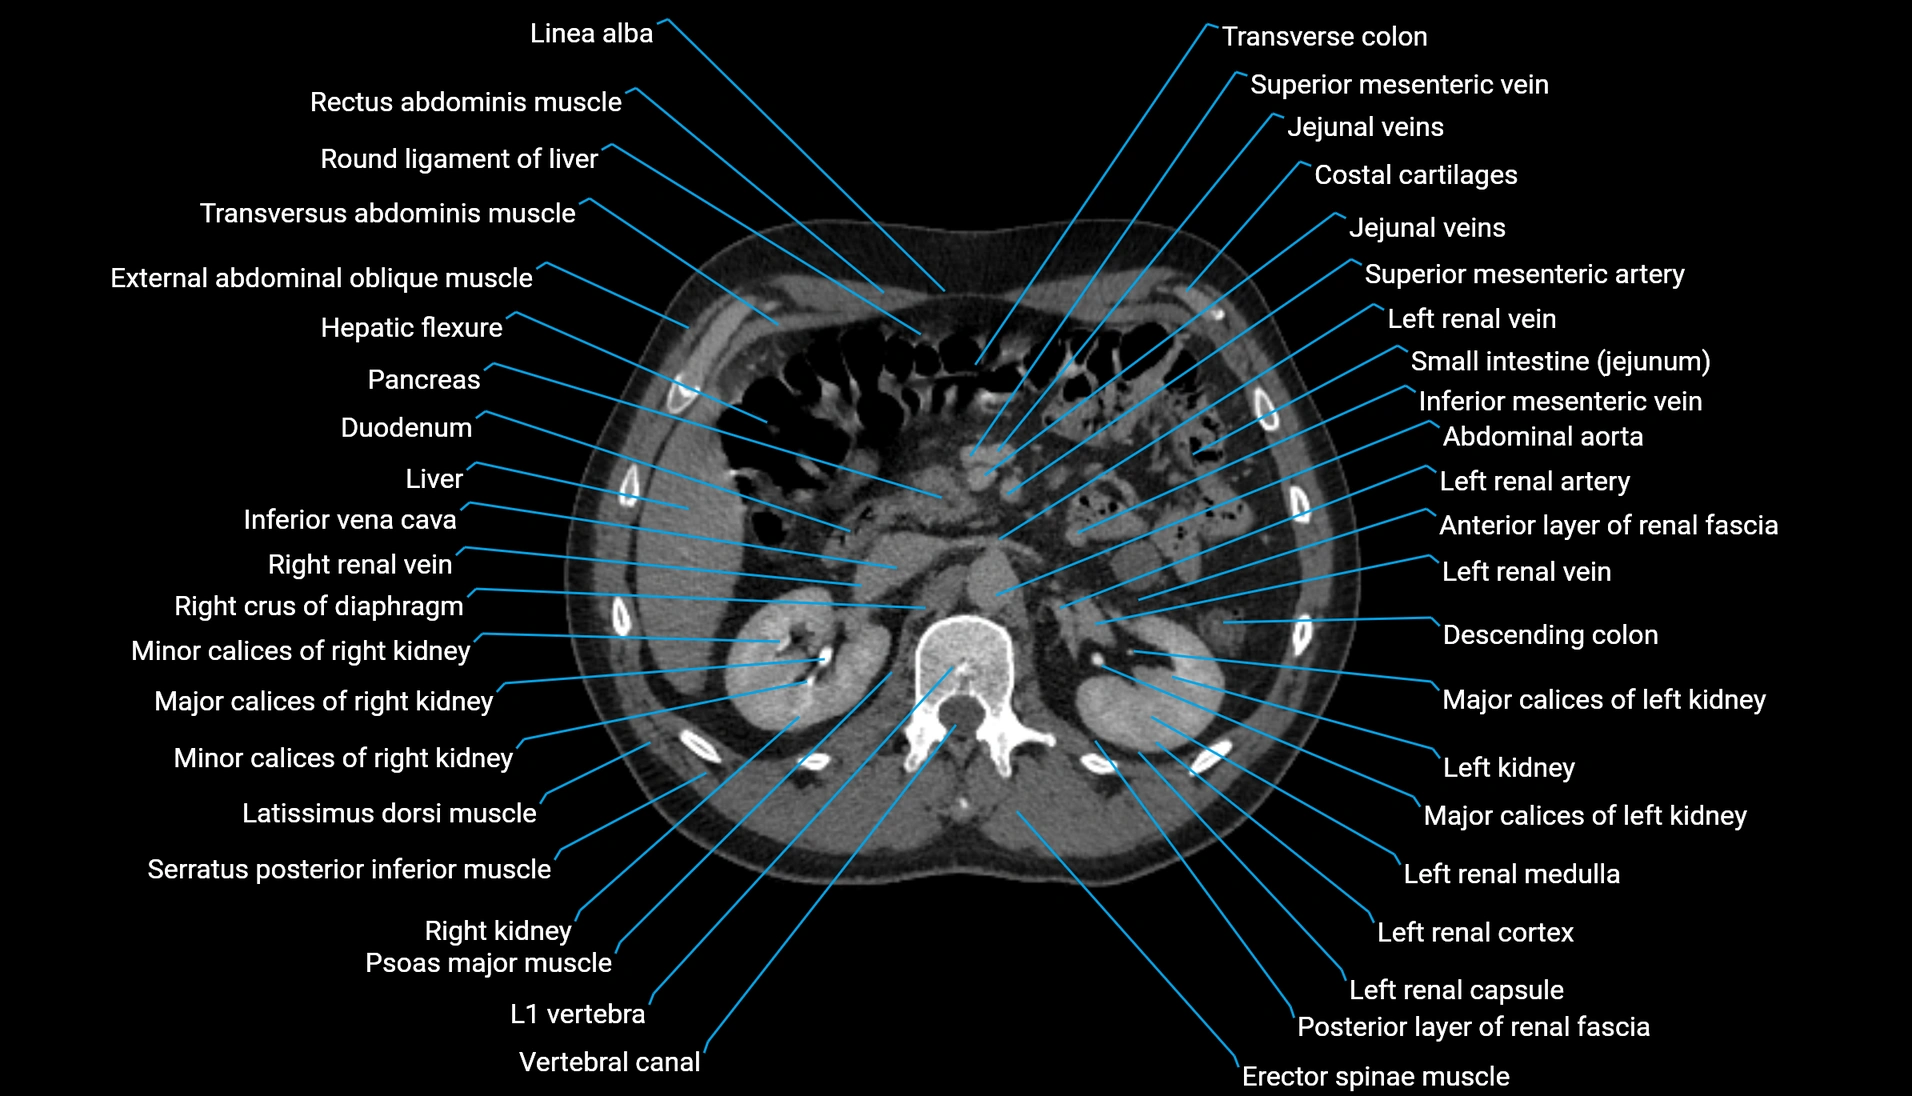

CT Appearance

Non-contrast CT:

-

Demonstrates cortical bone of acetabular rim in excellent detail

Detects fractures, dysplasia, retroversion, or bony overcoverage (pincer impingement)

3D reconstructions used in preoperative hip surgery planning

CT VRT 3D image

CT image